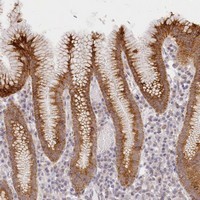

- Immunohistochemical staining of human stomach with MAP6D1 polyclonal antibody (Cat # PAB23199) shows strong cytoplasmic positivity in glandular cells at 1:50-1:200 dilution.

- Immunohistochemistry (Formalin/PFA-fixed paraffin-embedded sections)